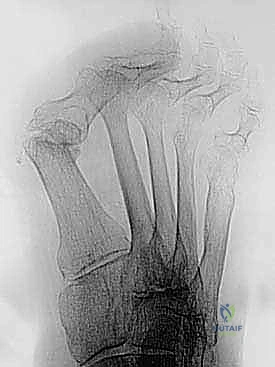

- التصوير بالأشعة السينية (X-rays): صور في وضعية الوقوف (تحمل الوزن) من زوايا متعددة لقياس زوايا التشوه بدقة وحساب مقدار الطول المفقود.

لضمان التئام العظام (وهو ما يستغرق عدة أسابيع)، يجب تثبيت المفصل والطعم العظمي بقوة شديدة. يستخدم الأستاذ الدكتور محمد هطيف أحدث الشرائح المعدنية المصممة خصيصاً لاندماج إبهام القدم (Anatomical Locking Plates) والمسامير التيتانيوم. يتم وضع الشريحة فوق المفصل وتثبيتها بمسامير تمر عبر الطعم العظمي لضمان ثباته المطلق.

7. الإغلاق والتحقق بالأشعة

يتم أخذ صور أشعة سينية داخل غرفة العمليات (Fluoroscopy) للتأكد من المحاذاة المثالية للإصبع، وتصحيح زاوية الارتفاع، والموضع الدقيق للمسامير. بعد ذلك، يتم إغلاق الجرح بخيوط تجميلية ووضع ضمادات معقمة وجبيرة واقية.